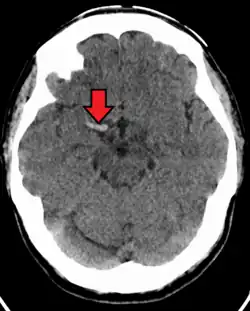

| CT scan without intravenous contrast showing hyperdense aspect of the right middle cerebral artery, indicating thrombus within the vessel | |

In medicine, the dense artery sign or hyperdense artery sign is an increased radiodensity of an artery as seen on computer tomography (CT) scans, and is a radiologic sign of early ischemic stroke.[1] In earlier studies of medical imaging in patients with strokes, it was the earliest sign of ischemic stroke in a significant minority of cases.[2] Its appearance portends a poor prognosis for the patient.[3][4]

The sign has been observed in the middle cerebral artery (MCA),[4] posterior cerebral artery (PCA),[5] vertebral artery,[2] and basilar artery;[6] these have been called the dense MCA sign, dense PCA sign, dense vertebral artery sign, and dense basilar artery sign, respectively.